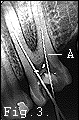

The dentist's drill should have little difficulty removing the decay and entering the soft cavity (pulp) but how are the fine canals containing the vessels and nerves to be emptied of their contents without leaving debris behind that could lead to problems? Easy - rake them out - or said more accurately: put fine metal wire rasps down the nerve canals and scrape them out. You can see in (Fig.3) two such tiny tools inserted through the exposed pulp and up into the two nerve canals. Although this image has been reduced in size you can just see the zig-zagged edge of the tool indicated by (A).